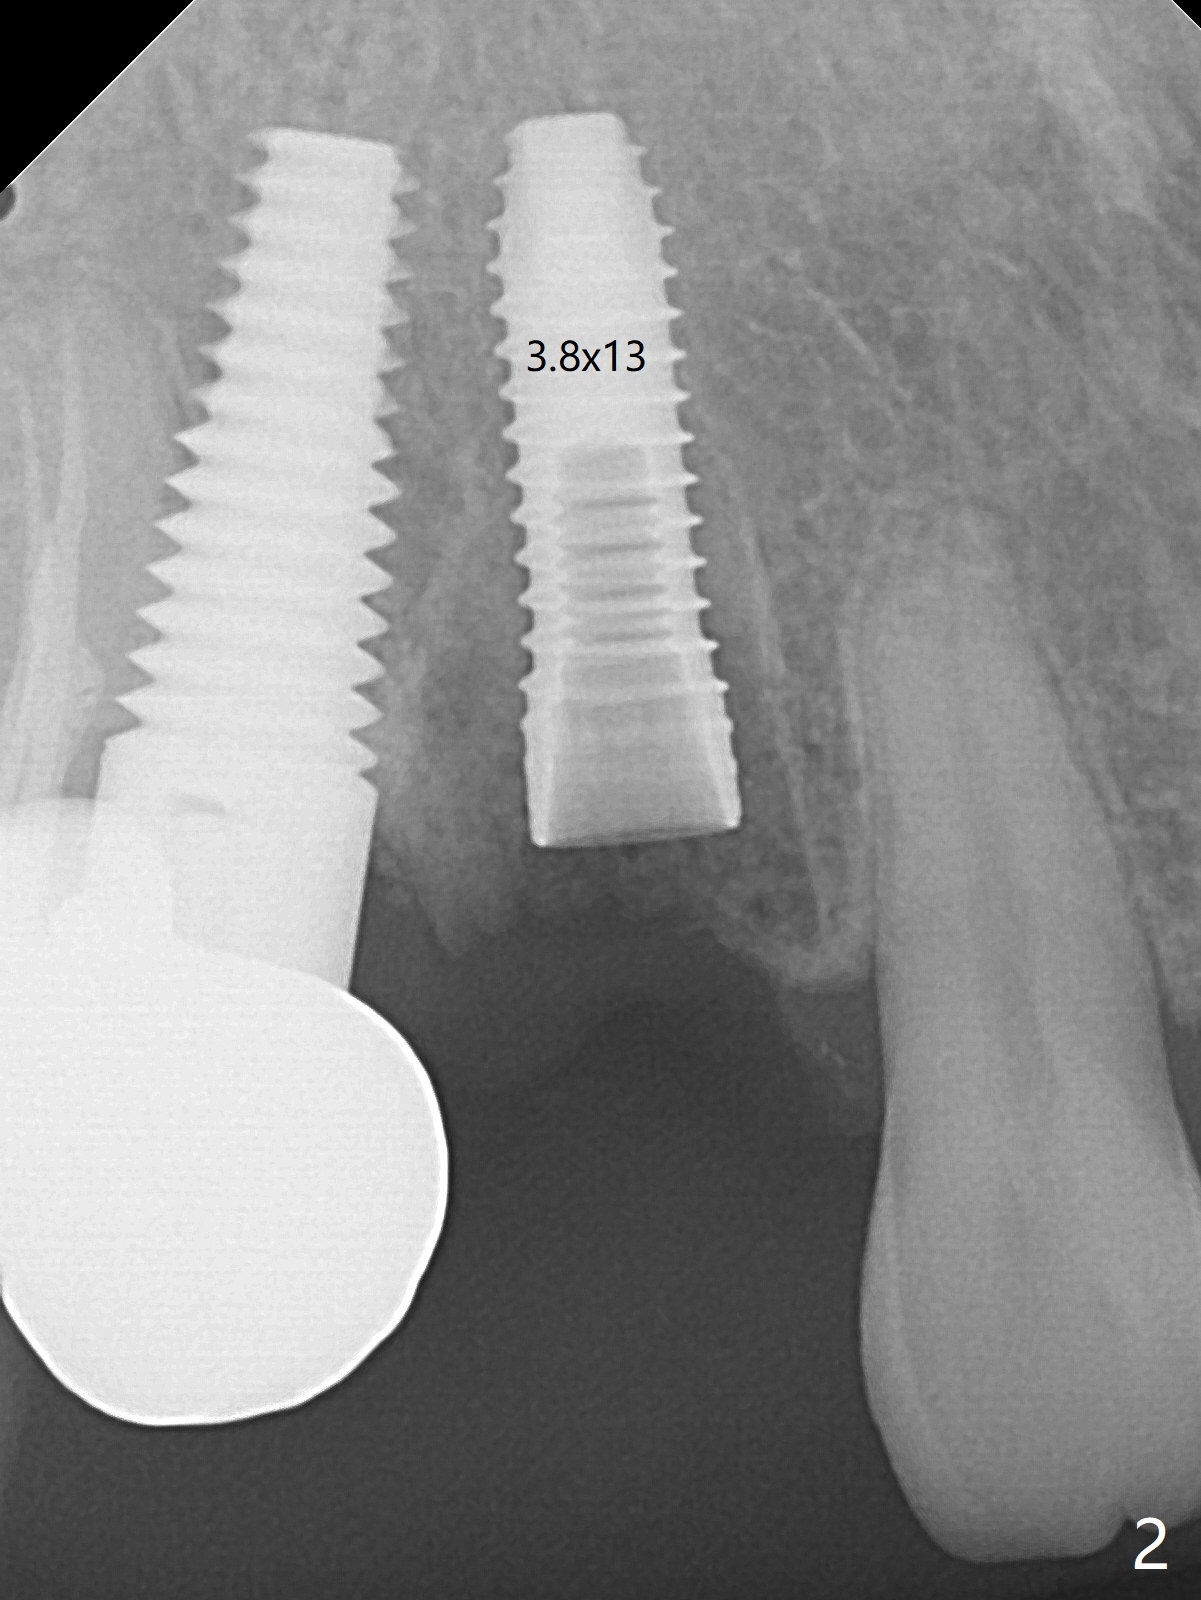

When the recemented crown at #6 is removed, the post is found to have been fractured. When the tooth is extracted, the socket walls are found intact. After moving the initial osteotomy (Fig.1) mesial, a 3.8x13 mm implant is placed (Fig.2). Clinically it appears supracrestal lingually. So the implant is placed deeper, but a cemented abutment is incompletely seated (Fig.3 <). When a longer abutment is used (easy grasping), it is seated completely (Fig.4). Then sticky bone is packed (Fig.5 *). When an immediate provisional is fabricated and seated, PRF membranes are inserted into the remaining gap between the gingiva and the provisional. Free hand surgery takes time and more intraop X-ray. It is inconvenient with nervous patients. The socket heals 2 weeks postop (Fig.6). The provisional will be next relined and reseated. It is difficult to insert gingival retraction cord 3.5 months postop because of the deep mesial margin. When an abutment with longer cuff is placed, the packing is easier (no biologic width violation, Fig.7 (^: resorbed mesial crest), as compared to Fig.5). When the crown is cemented (un-esthetic due to failure of use of temporary abutment), the metal shows at #5 with gingival recession because of buccal placement (Fig.8-10). Bone resorption is severe between #5 and 6 (Fig.7), as related to large gingival embrasure (Fig.9 *). When #5 crow is redone, move the gingival margin apical and fabricate provisional.